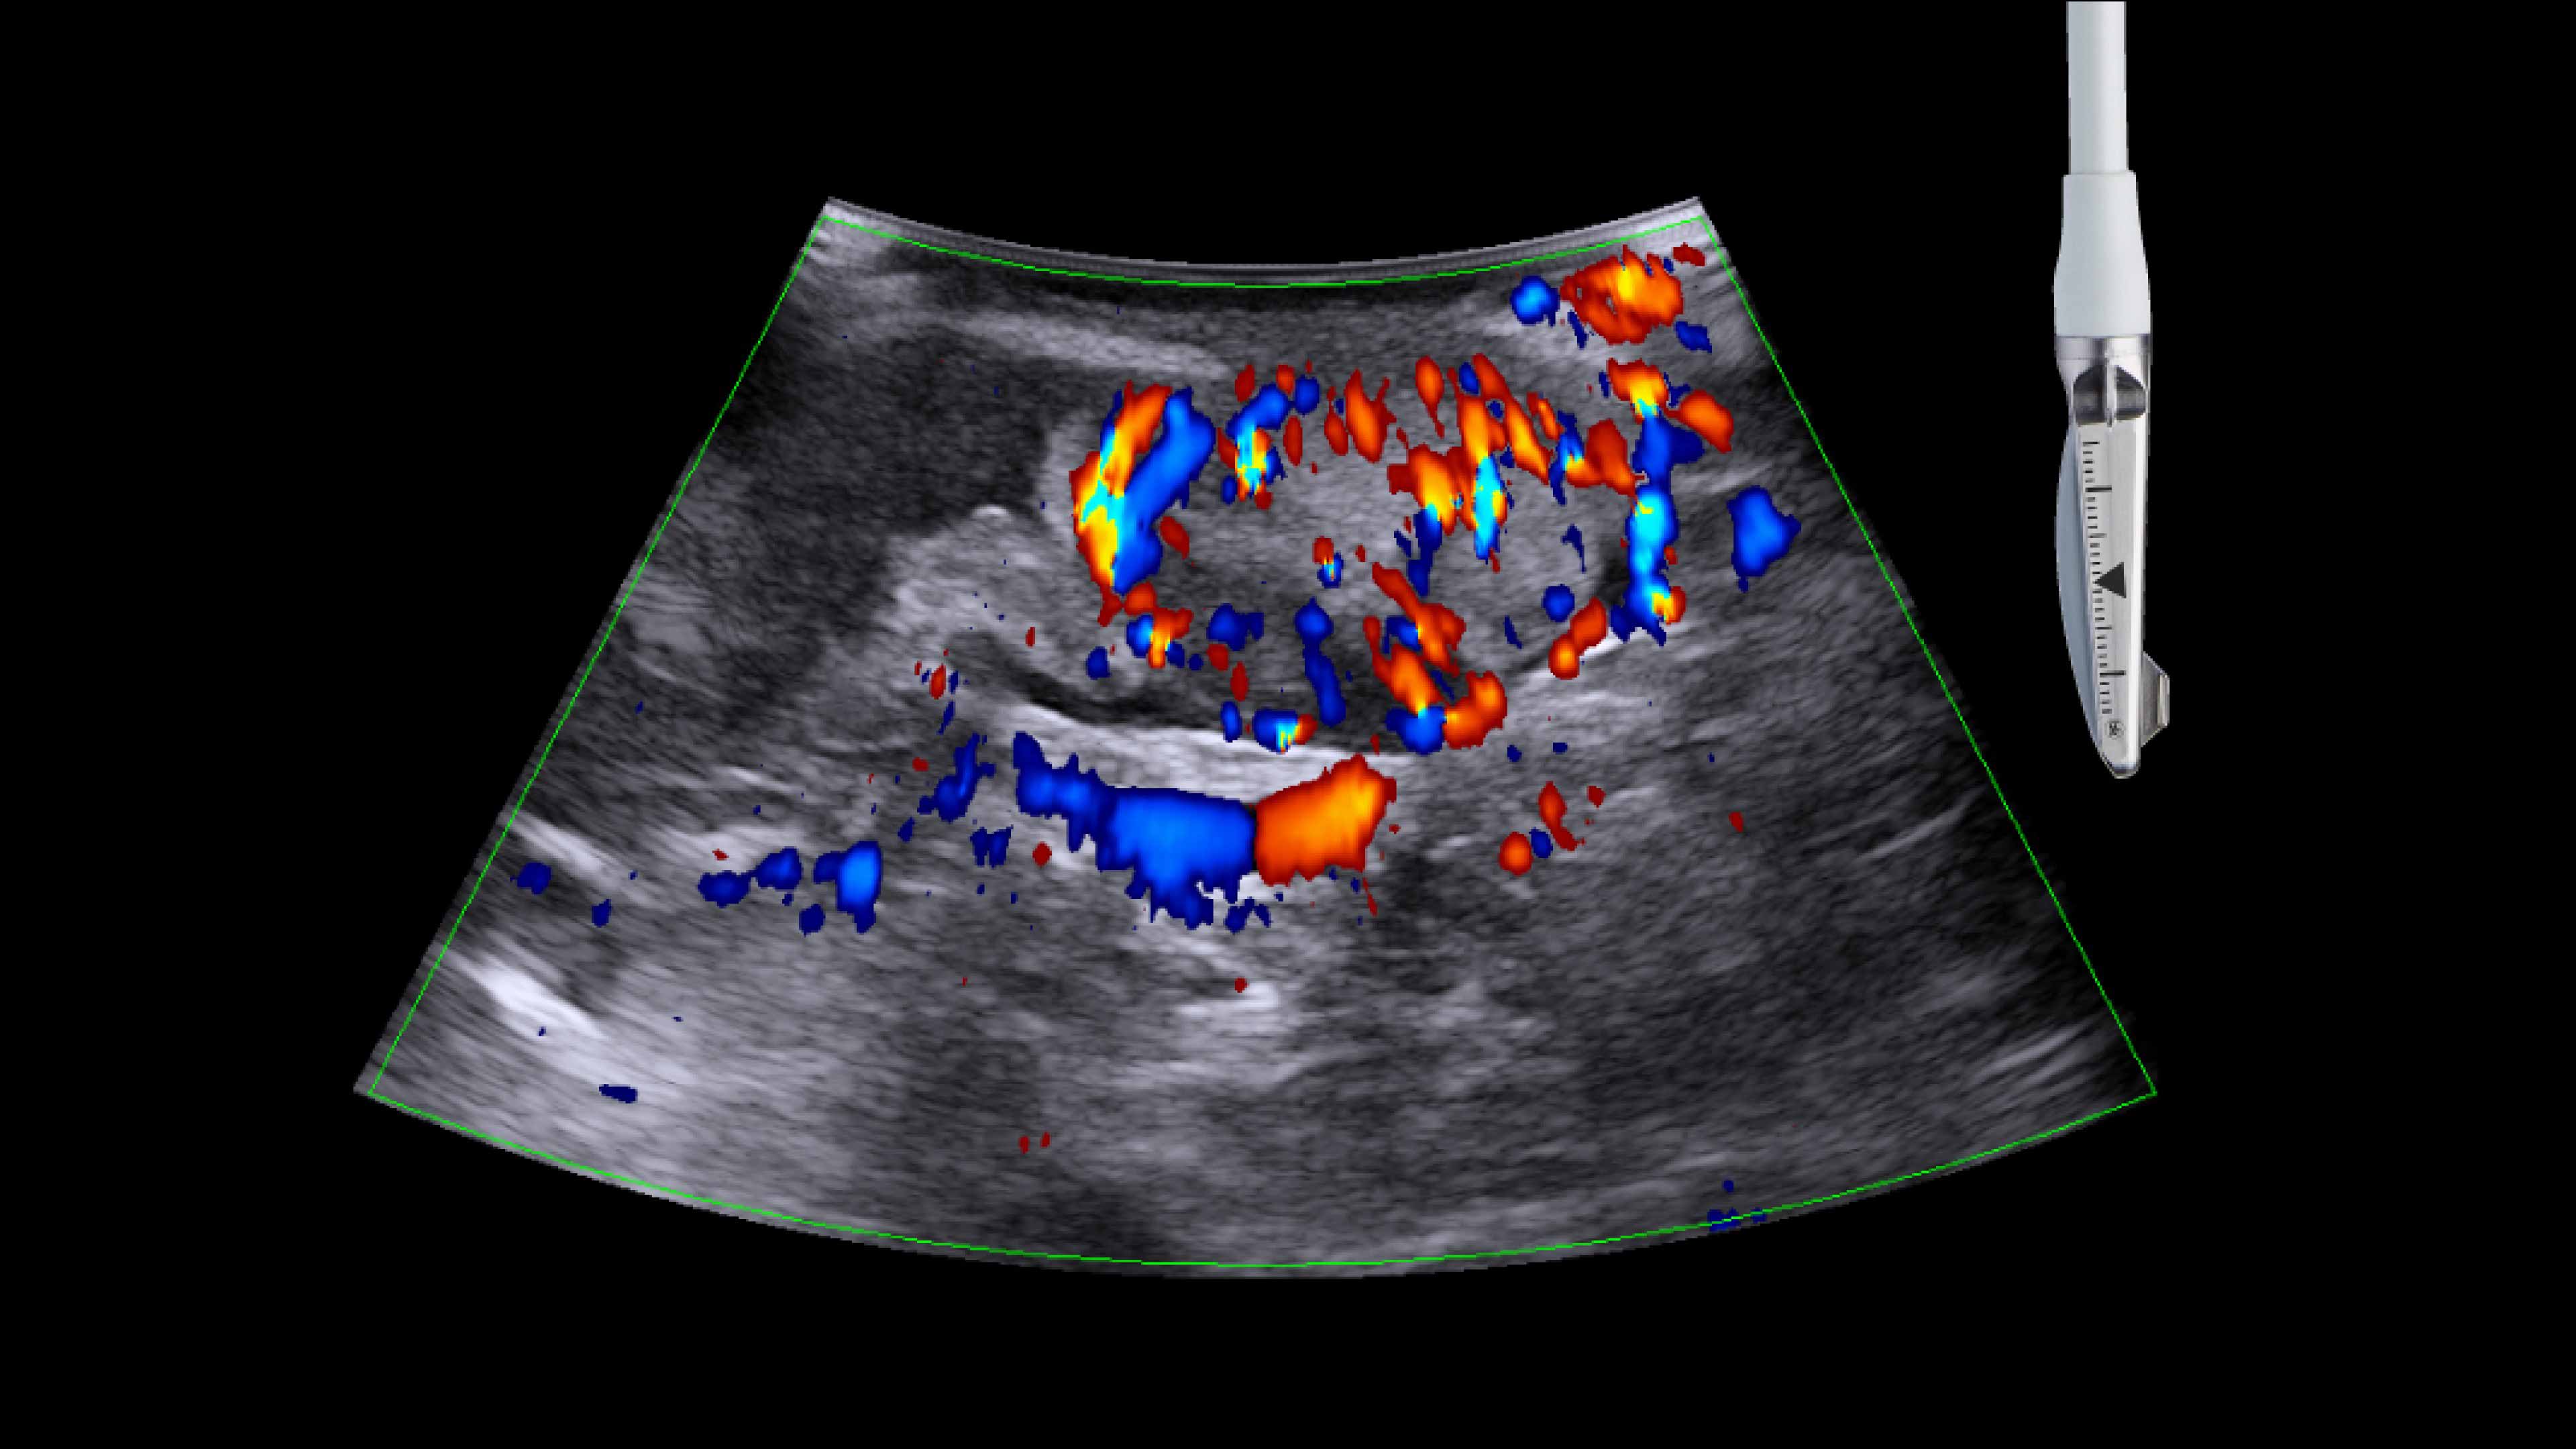

• iUS uses color flow doppler to help differentiate between vessels and ducts and is overall effective at imaging difficult cases such as inflammation or fibrosis .¹,⁴⁻⁶